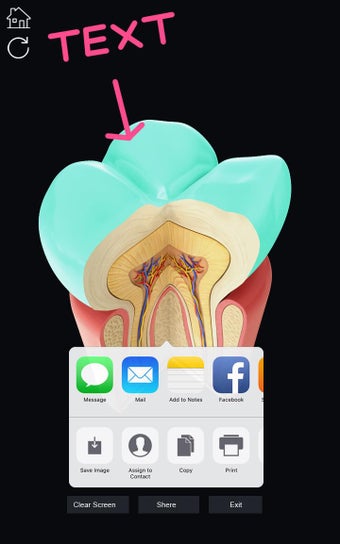

Esta aplicación es un modelo 3D de los dientes, que contiene muchas partes y muestra las condiciones dentales. Cada parte tiene un nombre y una función. Puedes mover la cámara alrededor del modelo para obtener una vista de 360° de las diferentes partes. Puedes hacer zoom para ver mejor cada parte. También puedes rotar la cámara para obtener una vista diferente del modelo.